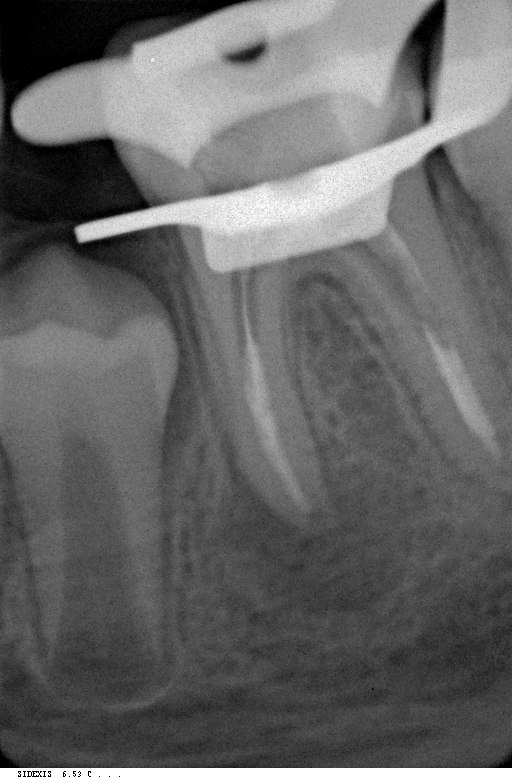

*Далее-берутся рентгенограммы. Во время Эндодонтического лечения берутся несколько наборов рентгенограмм. В начале по крайней мере два необходимы.

* Эндодонтическое лечение в обязательном порядке определяется электронным устройством под названием apex locator и проверяется с помощью нескольких рентгенограмм, сделанных с иглой в каждом корневом канале.

До лечения Во время лечения Спустя 6 мес